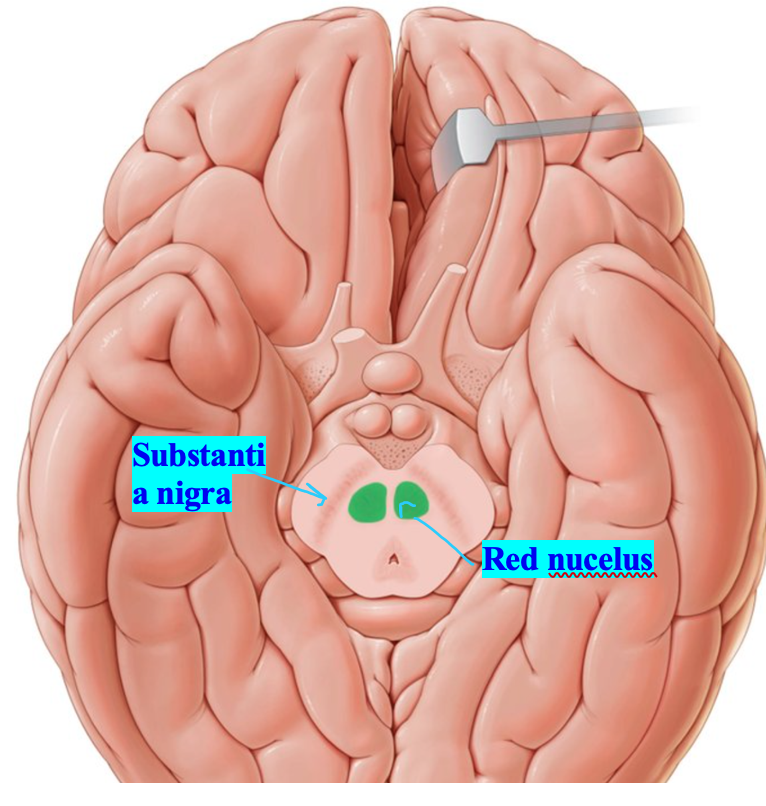

What is the structure called highlighted in red

Substantia nigra